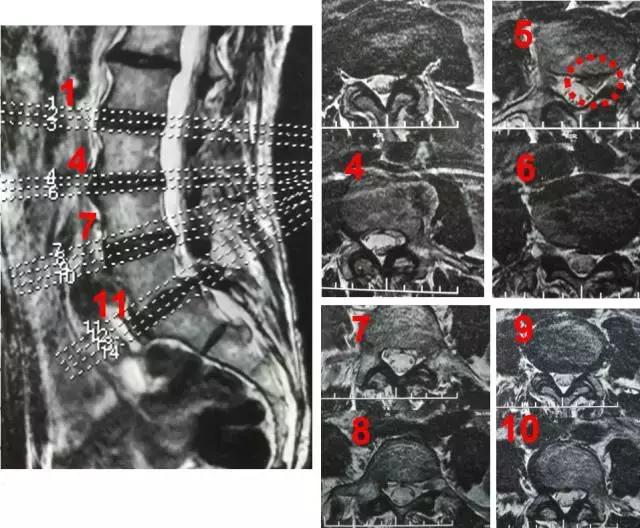

术前影像学检查:

X片报告:腰椎侧弯

MRI报告:L3-4椎间盘突出;L4-5及L5S1椎间盘膨出

3D CT报告:L3-4椎间盘左后方脱出,压迫硬膜囊及左侧神经根,左侧侧隐窝狭窄; L4-5及L5S1椎间盘膨出,双侧侧隐窝狭窄

腰4-5椎间盘突出症(旁中央型,向上游离型,累及左侧腰4神经根侧隐窝段)。

定位分析:症状及体征定位左侧腰4神经根可能性大;MRI及CT三维重建报告未考虑脊柱侧弯影像,误将明显突出L4-5节段定位于L3-4节段。

3、本例合并脊柱侧弯,影响了MRI和CT影像节段的判断,术前报告突出节段有误,因此术前需结合全面的病史、详细的查体、细致的影像学分析才能作出综合判断;